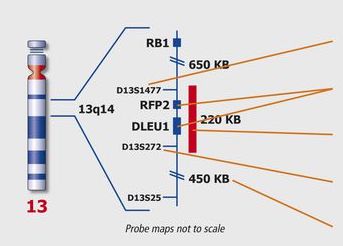

Kreatech FISH Probes

Kreatech FISH probes are the latest in advancements in FISH probes. Developed with the use of REPEAT-FREE technology, Kreatech FISH probes eliminate the use of Cot-1 or blocking DNA, providing a clearer background and a brighter signal.